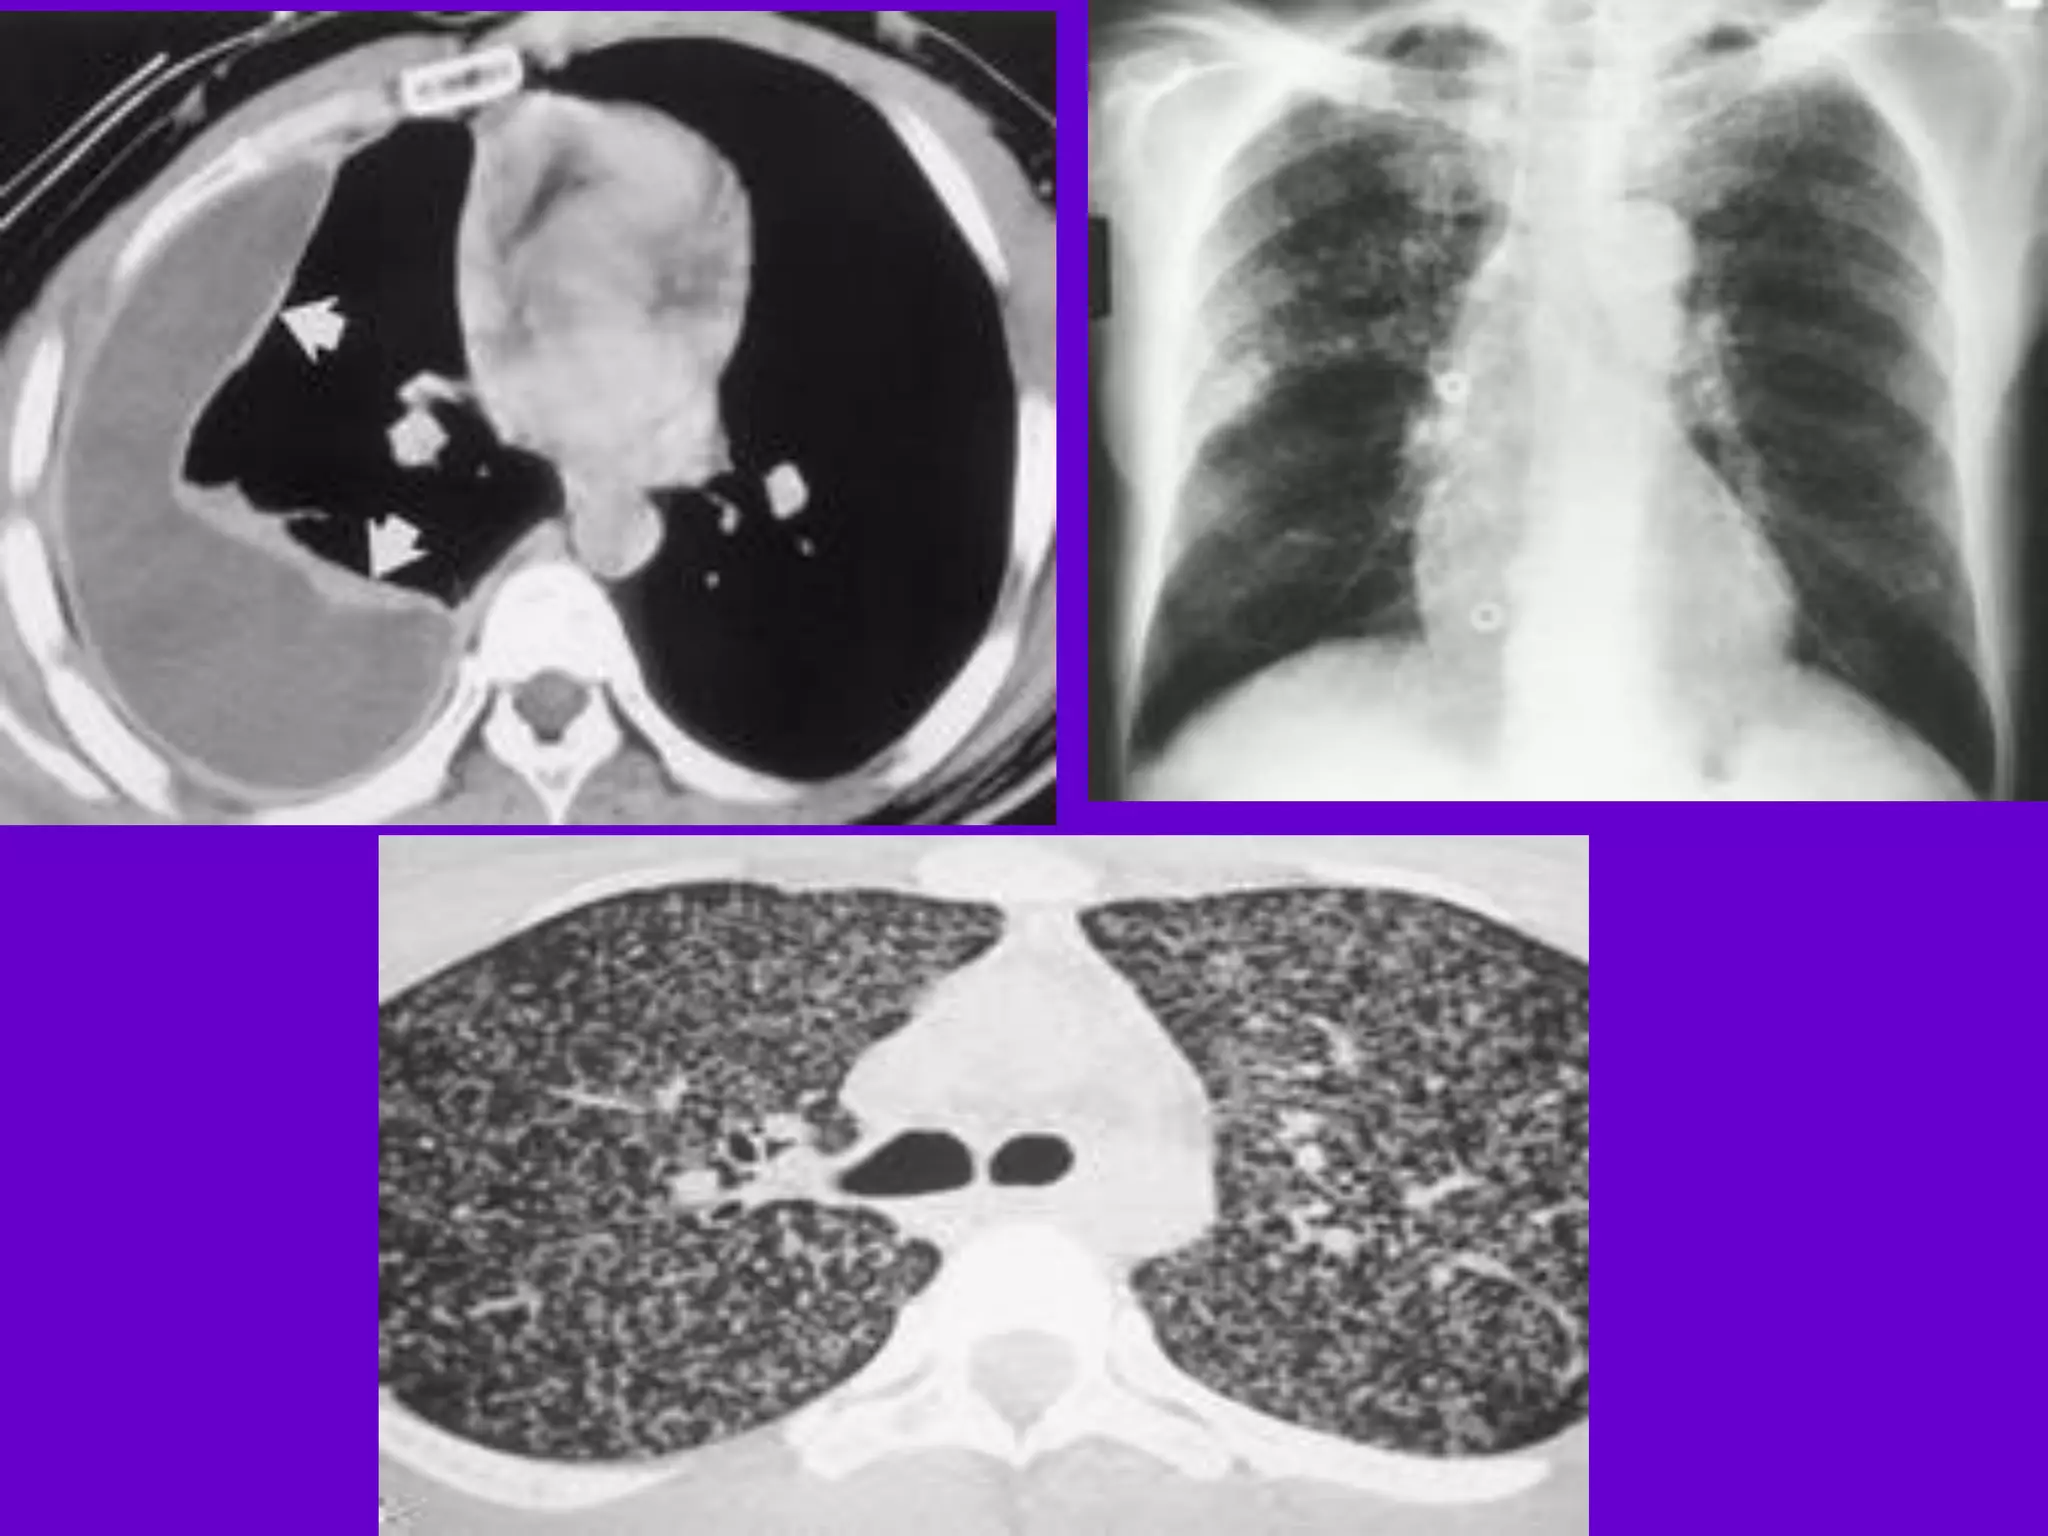

Bronchopneumonia

􀂄

On CT it is usually B/L and widespread,

not always

symmetrical involvement of lungs.

Hilar and Mediastinal

Lymphadenopathy

CT and MRI depict the hilar and

mediastinal LN

equally well.

􀂄 Calcification in the nodes is however

better seen on

CT.

􀂄 Necrosis is seen as focal areas of low

attenuation on

a CECT.

􀂄 On MRI focal necrosis is seen as areas

of increased

signal intensity on T2W images.

EBTB

HRCT is sensitive in the detection of

early

endobronchial spread of disease.

Miliary TB

􀂄 Earliest form of miliary TB is detectable

on HRCT.

􀂄 Coalescing nodules result into patchy

irregular

opacities and HRCT shows this variation

effectively

and has been described as “snowstorm

appearance”.

􀂄 HRCT shows cavitation, which is not

evident on plain

CXR.

Pleural Effusion 􀂄

􀂄 CT is sensitive to diagnose and define

even minimal

pleural effusion/pleural calcification.